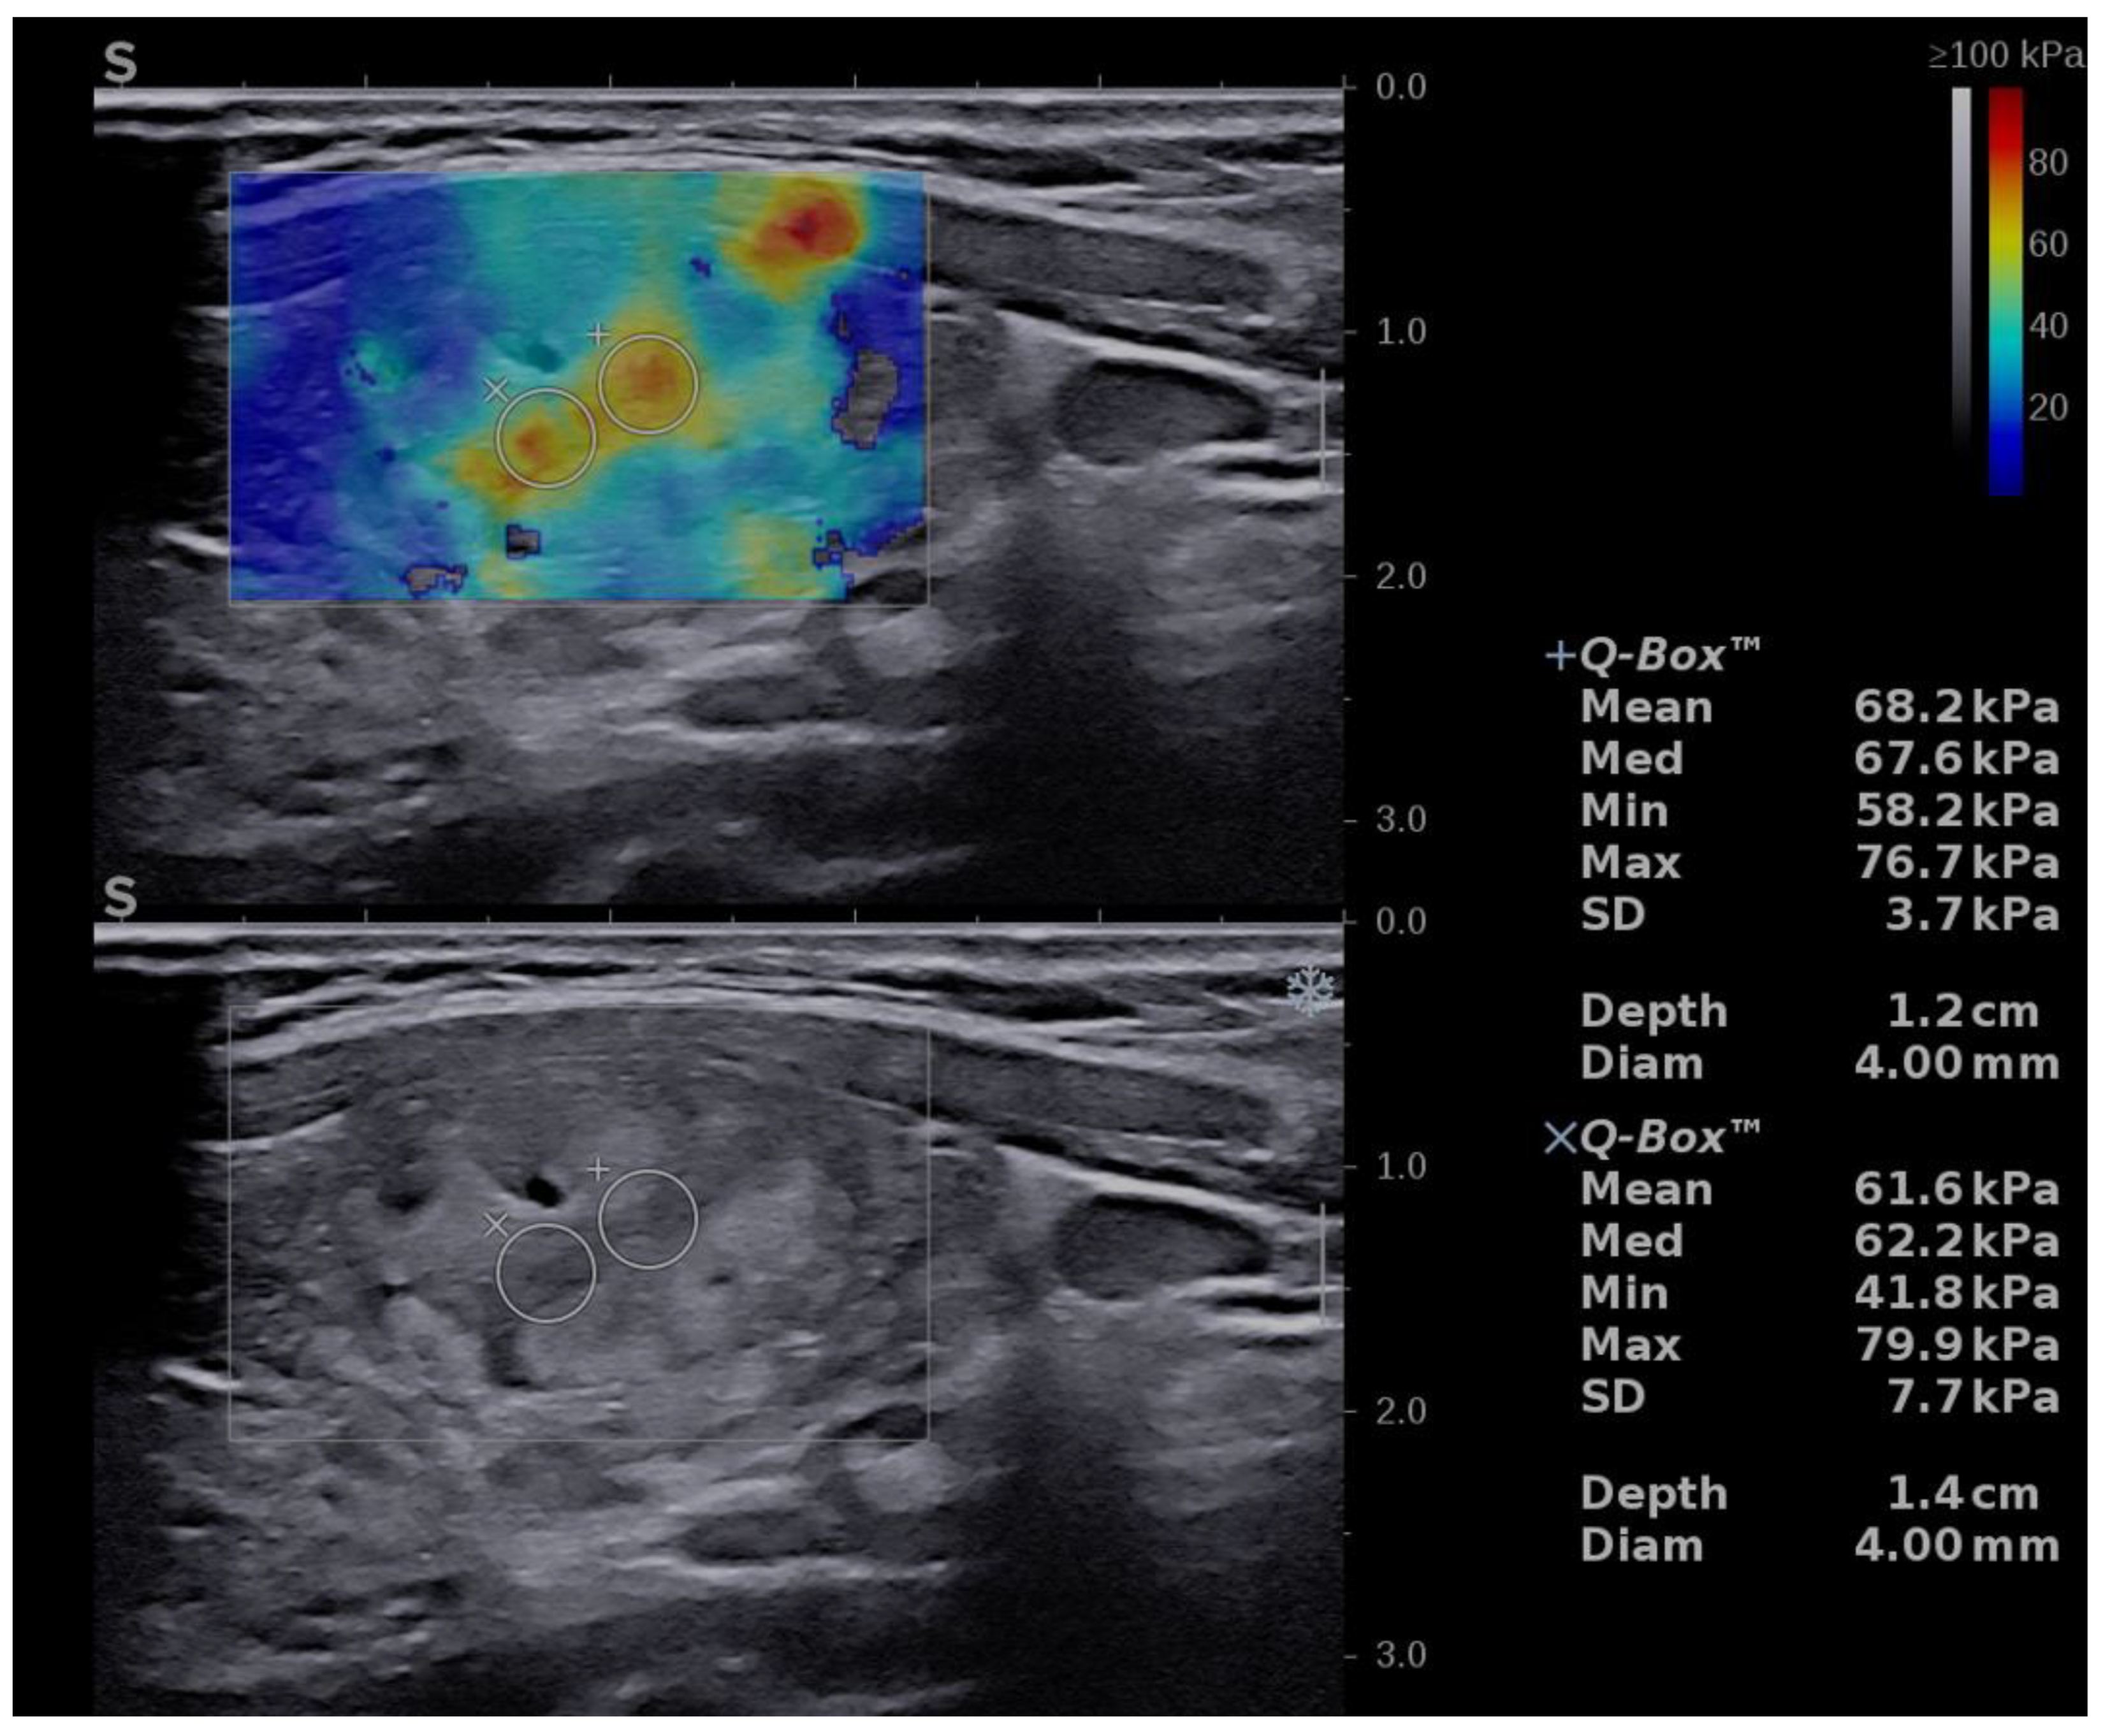

For the image acquisition, the box was adjusted to include the entire lesion. To acquire a stable, reliable elastogram, the examiner held the probe still for about 5 s and avoided applying external pressure. The machine does not provide a quality measure, so an experimented operator should perform the evaluation and avoid obtaining images with obvious compression artifacts such as “finger-like” artifacts or images with a completely red image (corresponding to high stiffness) []. Images lacking an SWE signal were also considered inadequate. The ROI was placed in the stiffest part of the nodule. The evaluation was uniform, and 5 values were registered for each lesion in longitudinal scans. The mean of the 5 measurements was considered in the analysis of the Max and Mean elasticity index (EI), measured in kPa. The QBox ratio was determined by comparing two ROIs, one in the stiffest displayed zone (without including obvious artifacts or calcifications inside the ROI) and one in the adjacent thyroid parenchyma or surrounding muscle, both placed at approximately the same depth, as shown in Figure 1. The diameter of the ROIs was set between 2–4 mm. Increased stiffness, documented by SWE evaluation, was considered as a high-risk parameter [,,,,].

Figure 1.

Transverse US scan displaying a soft thyroid nodule in the two-dimensional shear-wave elastography (2D-SWE) evaluation, first image (up): Mean elasticity index (EI) = 21.4 kPa, nodule-to-parenchyma QBox ratio = 1.3; and in the greyscale (2B) evaluation, second image (down): low-risk, isoechoic solid nodule, with a thin halo, well-defined borders, and no features of high risk.